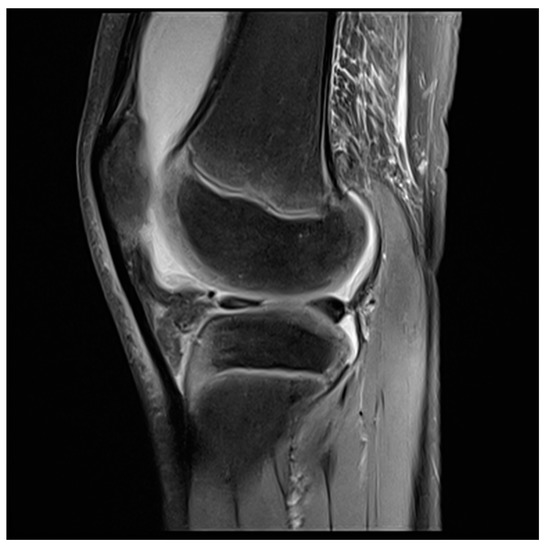

- Hirose, J.; Nishioka, H.; Tsukano, M.; Matsubara, S.; Usuku, K.; Mizuta, H. Matrix changes in articular cartilage in the knee of patients with rheumatoid arthritis after biological therapy: 1-year follow-up evaluation by T2 and T1ρ MRI quantification. Clin. Radiol. 2018, 73, 984.e911–984.e918. [Google Scholar] [CrossRef]